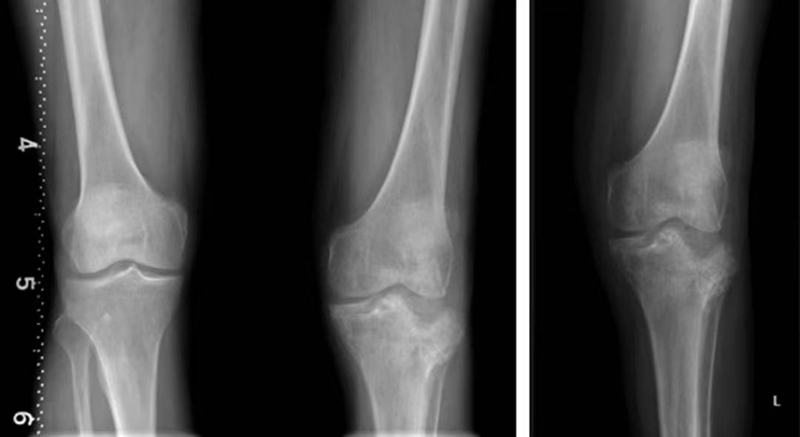

正常髌骨下极位于两侧股骨髁最低点连线之上,其下极在该连线近侧(图4)。髌骨高度大于其正常范围的最大值称为高位髌骨(图6),髌骨高度小于其正常范围的最小值称为低位髌骨(图5)。

图6 高位髌骨的正位X线片,髌骨下极过高地位于两侧股骨髁最低点连线之上